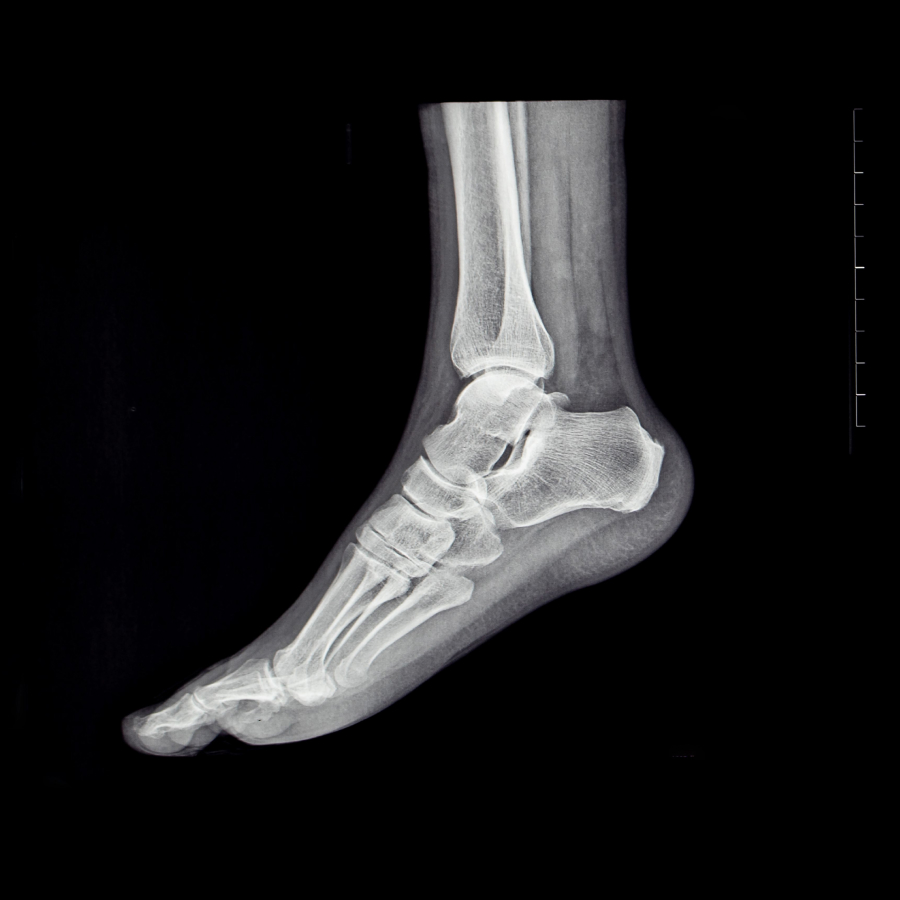

Pie